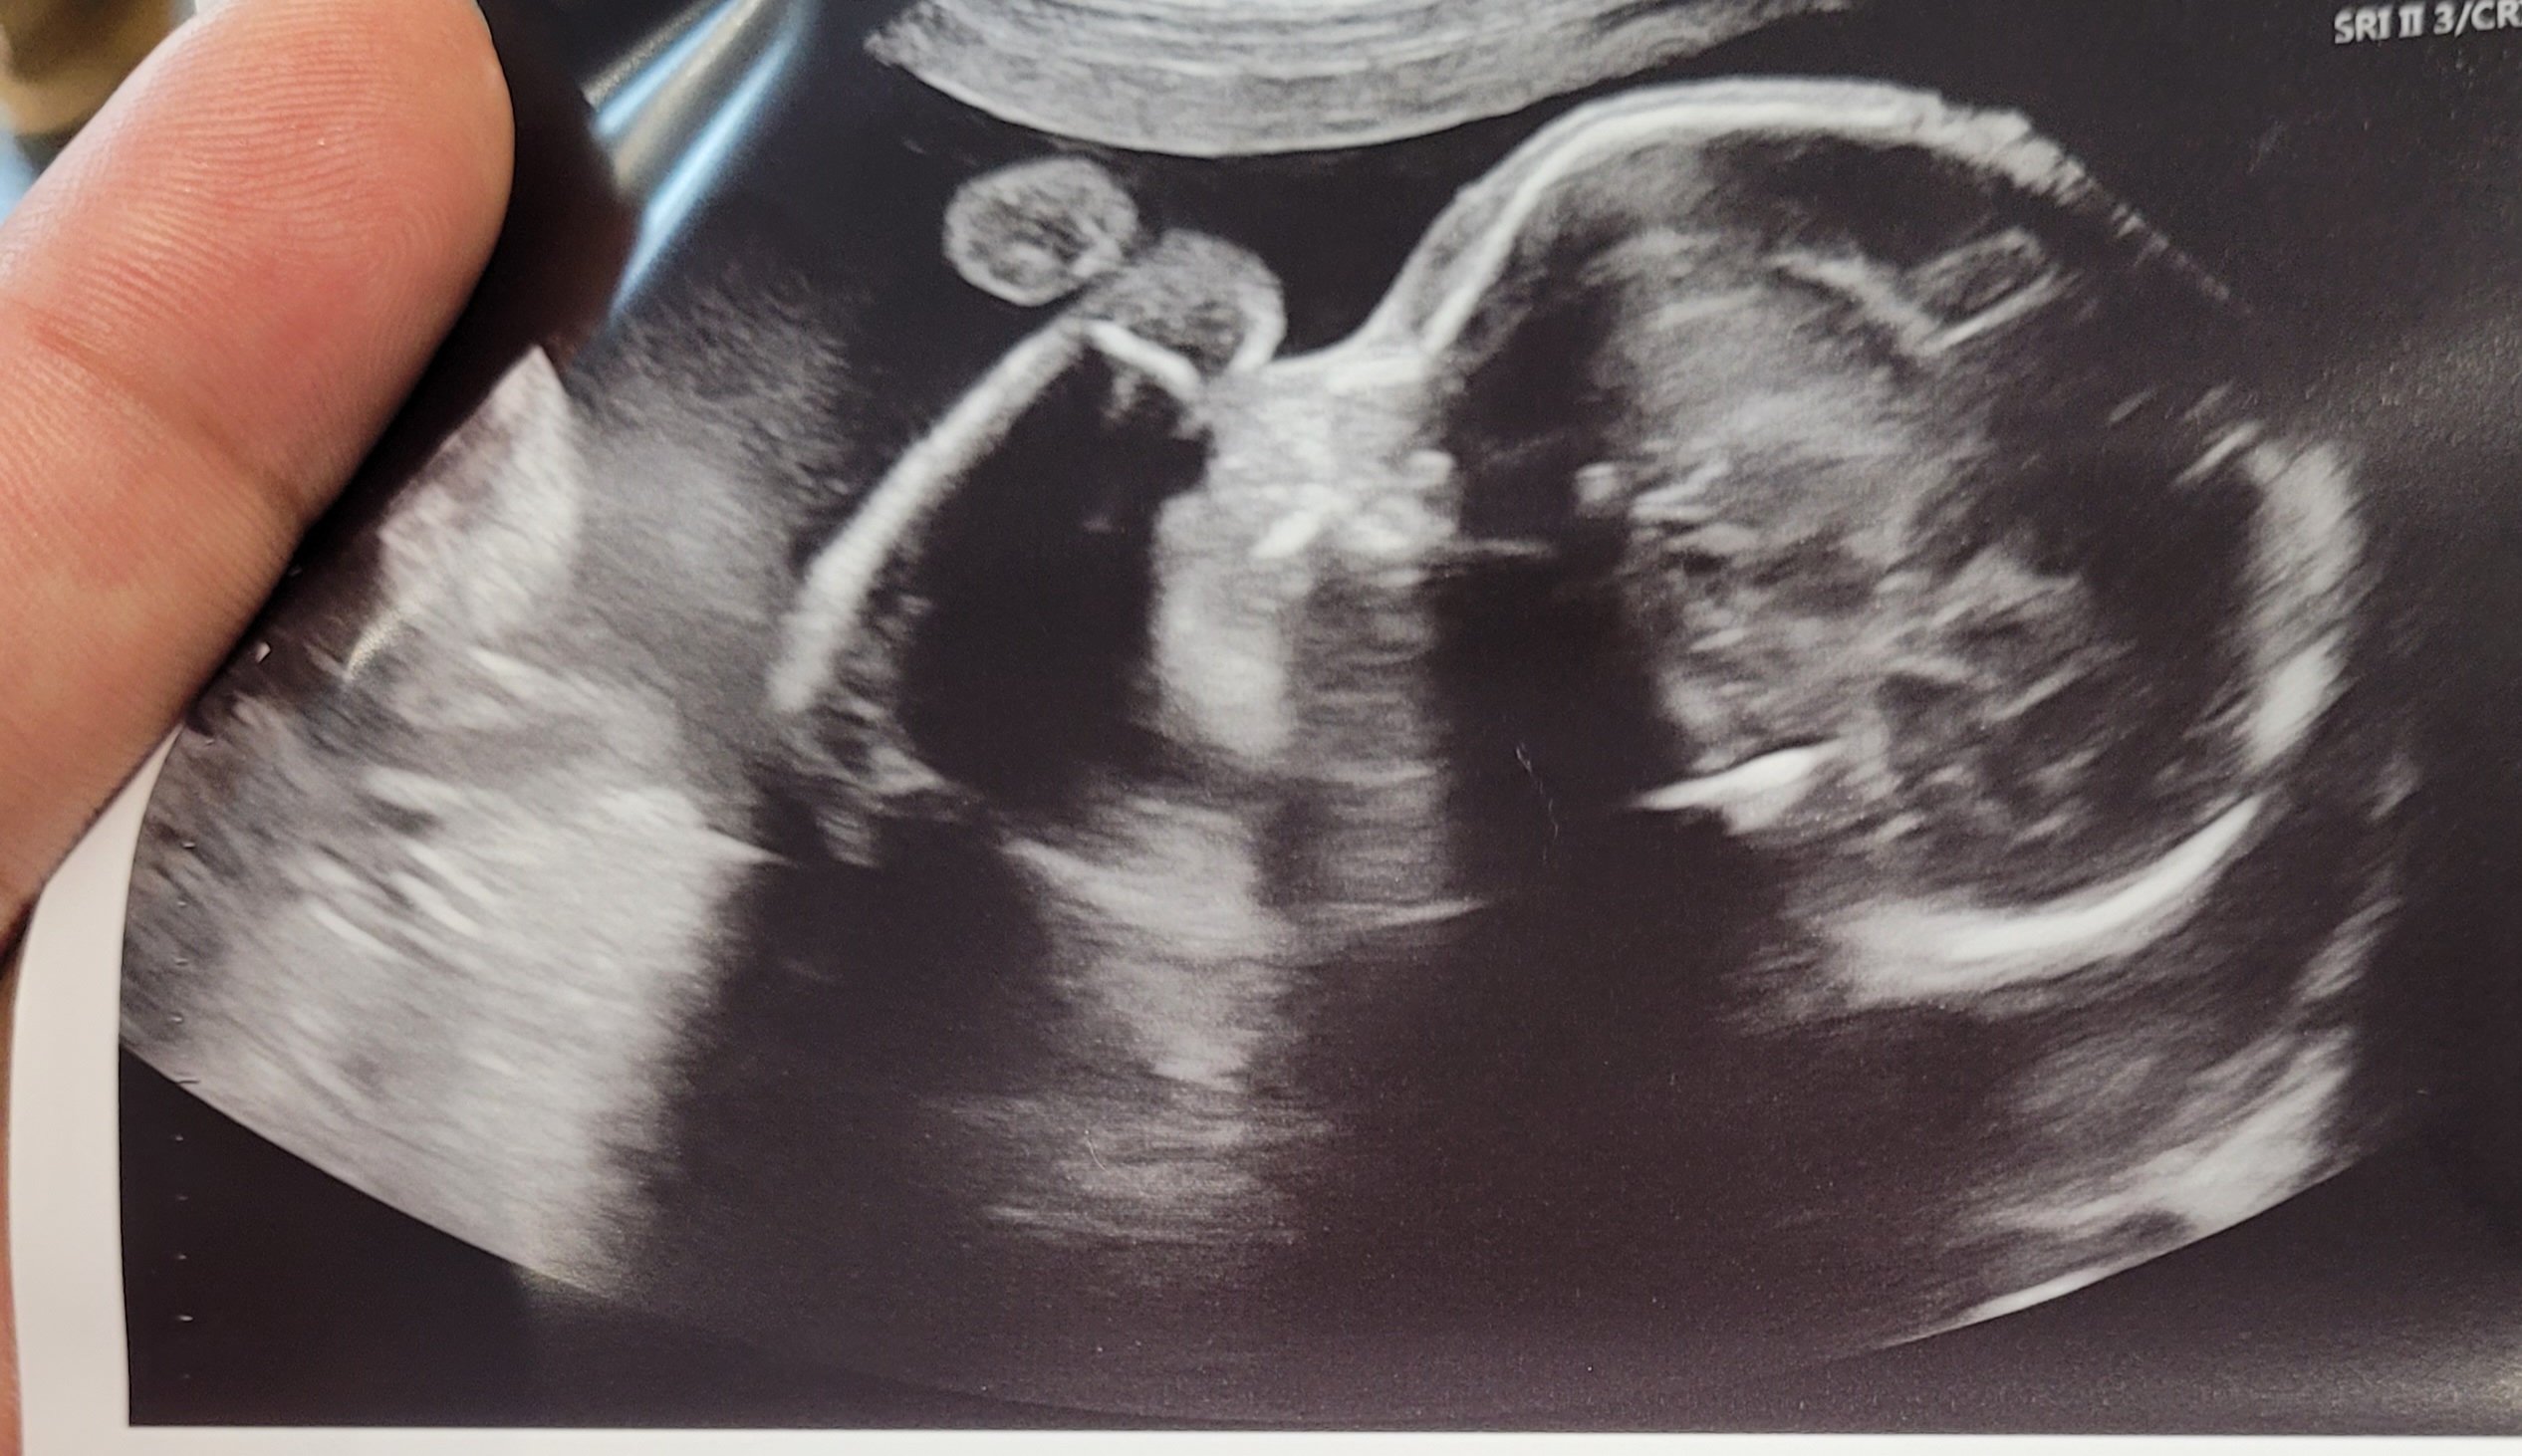

Nugget at 23+4. We didn’t get 3D with my first so this is awesome!

Me: 26 DH: 25

DS1 -- 9/30/2016